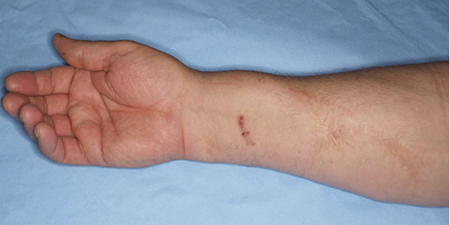

Cheiralgia%20Figure2.JPG

Figure 2. Post-trauma scar

The patient had a history of a penetrating trauma in the relevant area during childhood. In addition, the patient emphasized a slowly enlarging palpable lesion which occurred in concert with the presented symptoms. Physical examination demonstrated a palpable mass beneath the distal part of the scar (Figures 1, 2).